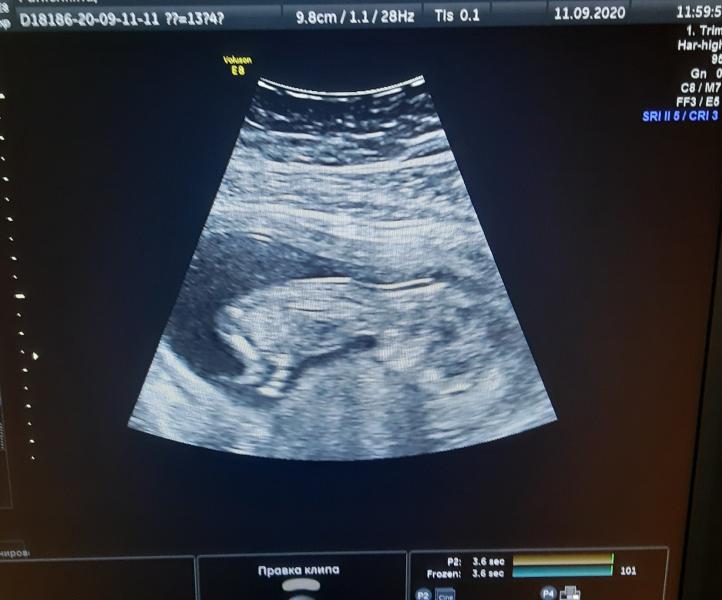

Мой маленький или моя маленькая 💞

Мне уже интересно кто в теремочке живет ))))

Такой маленький и шустрый уже ,бежал(а) куда то )

Врач такой противный ,вообще ничего не сказал ,я спросила кто там ,он сказал ребенок 😁😁он снохе моей говорил что не видно до 8 месяца ,потом она случайно попала к заведующей ,и она ей сразу сказала что девочка .

А тебе разве не сказали кто там? Сейчас вроде уже можно увидеть.